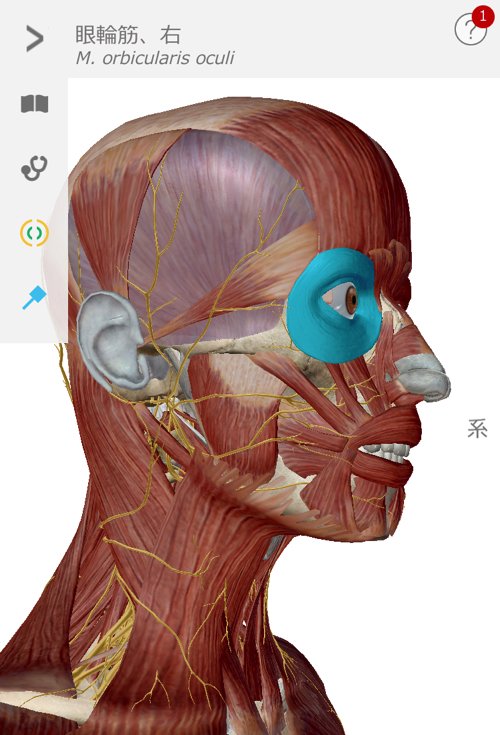

目が疲れて来るとコメカミから側頭部付近が固くなってきます。

目に関わる筋肉や水晶体・首や肩の筋肉なども固まっていきます。

目の疲れは単純に目の周りの筋肉だけの問題ではありません。

まず側頭骨が自由になるように顔周りから耳周りの筋肉を緩めて調え